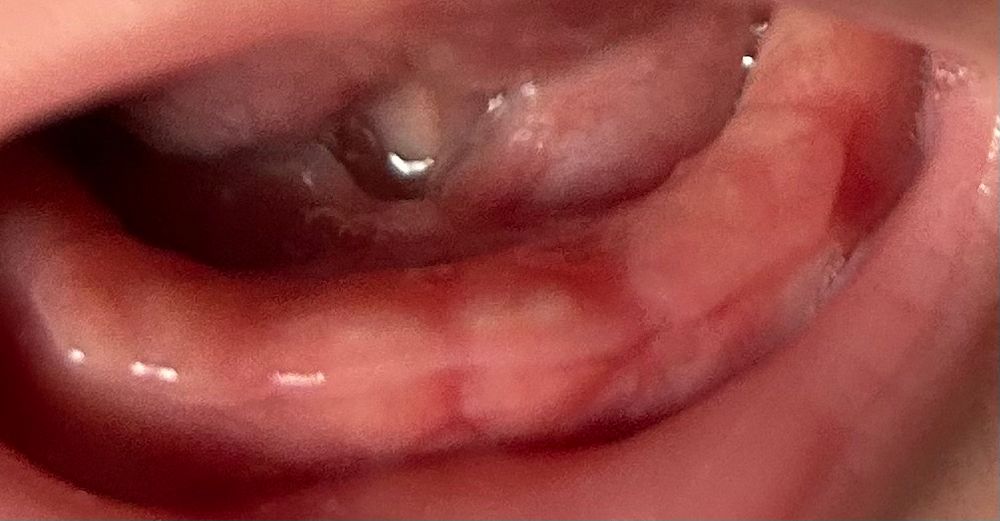

Юлия, просвечиваются. Десна припухли , да? То ли тень, то ли краснота, не пойму. Значит они, да

Юлия, конечно зубки, вон уже видны даже!

Юлия, зубки ваши видно😁у меня так же сейчас у ребенка видно что-то похожее на зубы. Но не могу сфоткать, не дает. У нас начались сопли, без температуры и ОРВИ, я водила к педиатру ОРВИ она исключитела, сказала на зубы. И сын постоянно язык начал под нижнюю губу засовывать и елозить там языком. Я тоже попробую завтра сфоткать что бы показать 😁